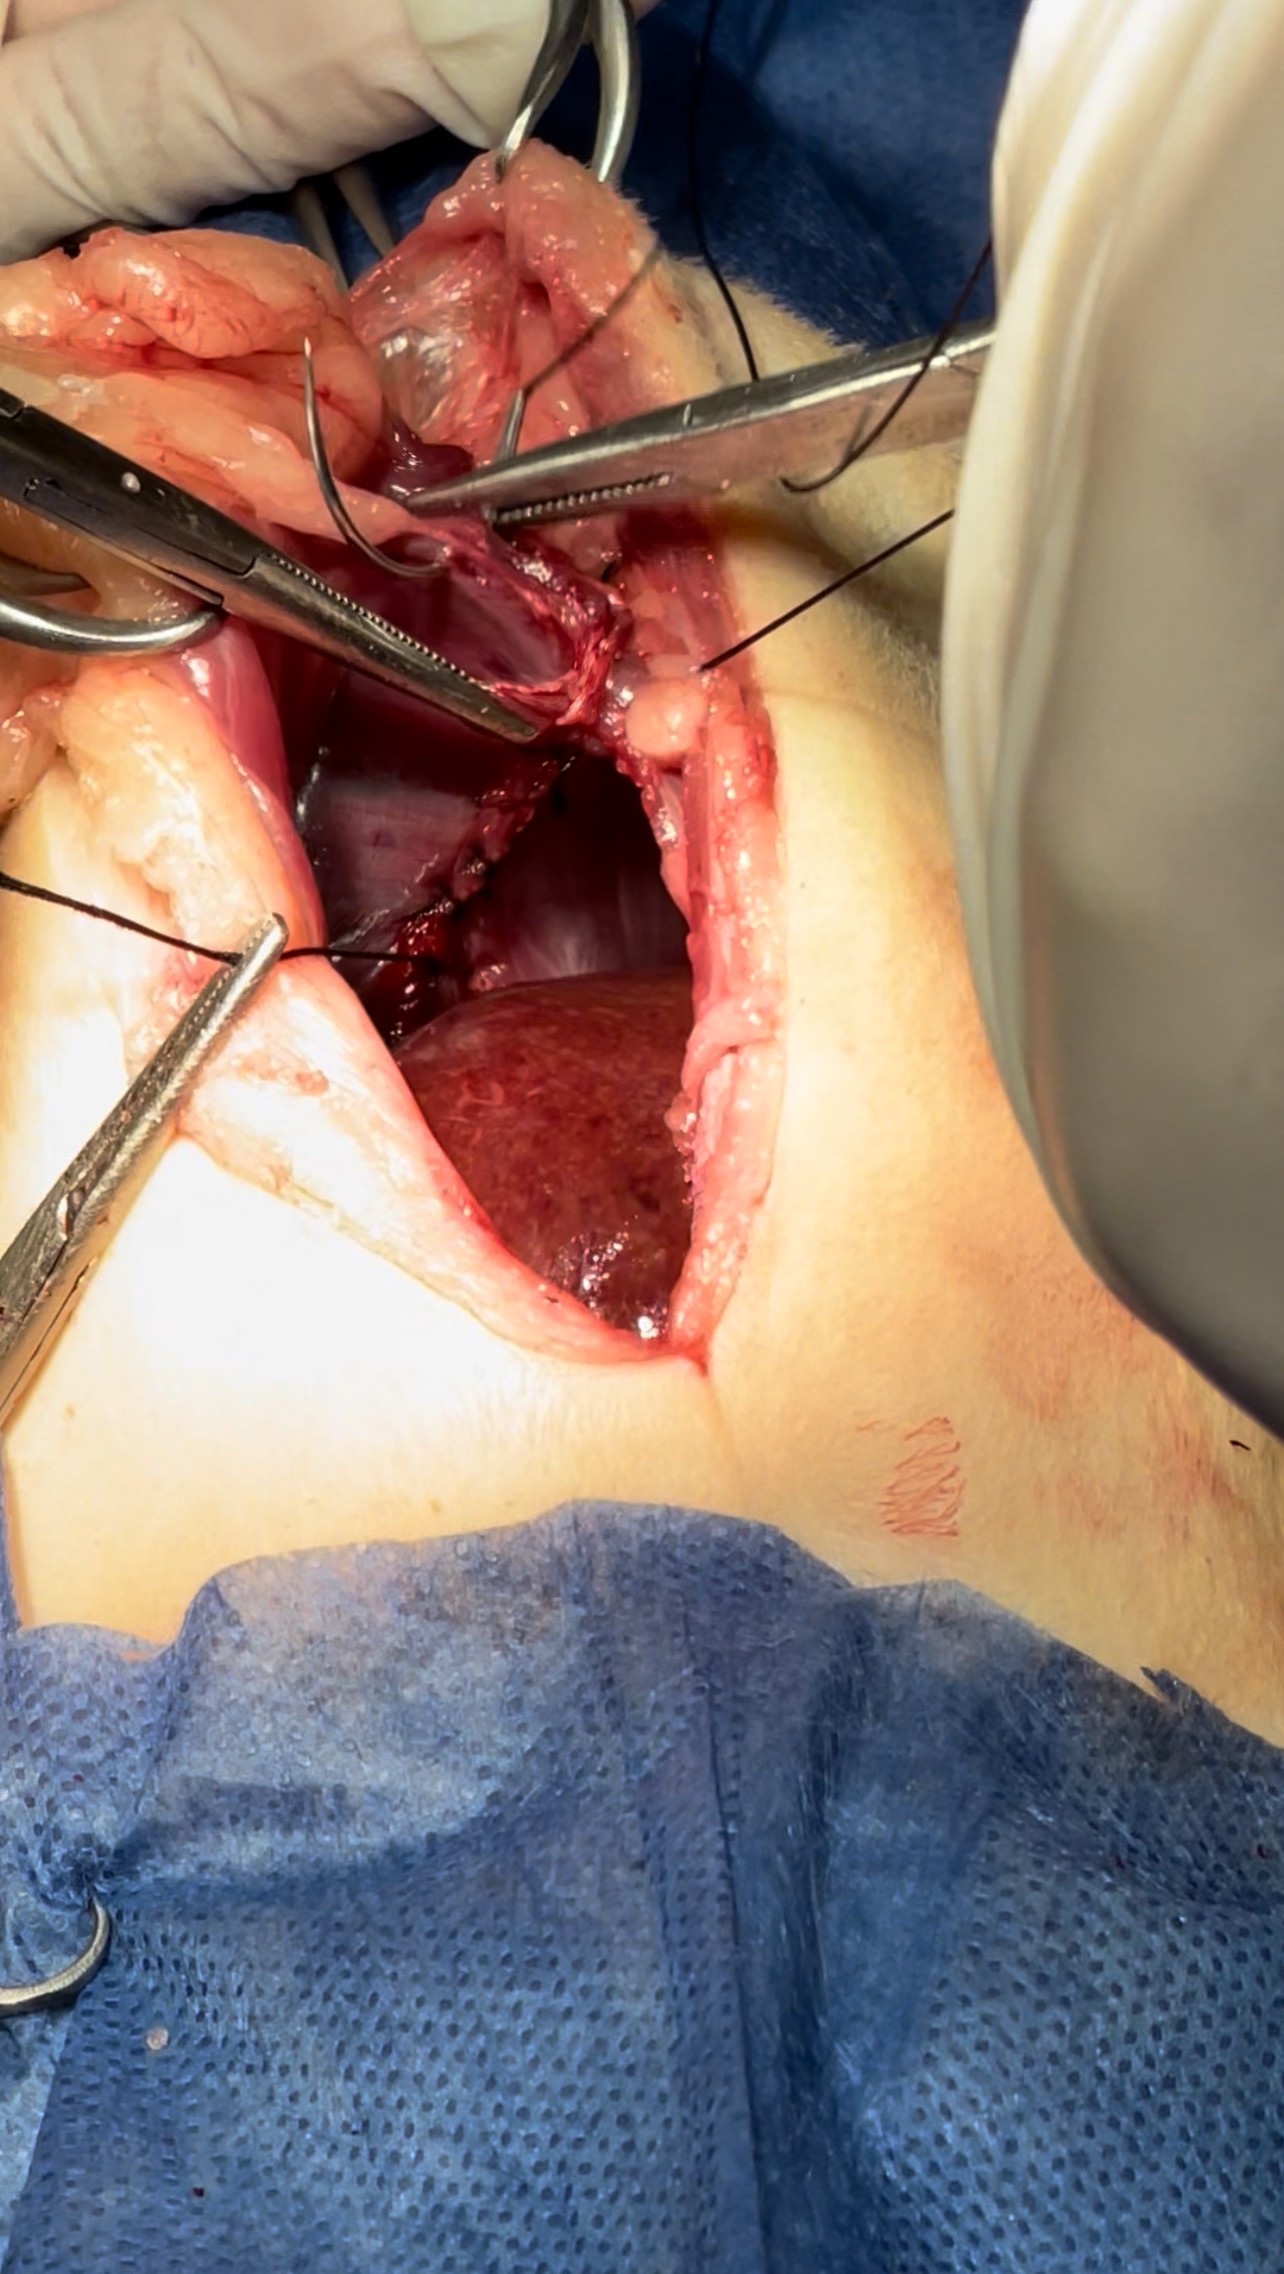

Dissection of the intraabdominal adhesive part of the live

Widening the herniation to allow organ exteriorization

Lacerations while dissection compressed with Gelfoam to minimize the parenchymal injury